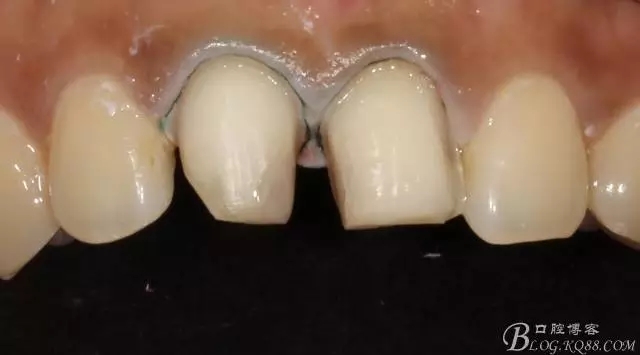

備牙后11(因扭轉(zhuǎn)制牙有點(diǎn)多,還是露牙本質(zhì)了)

局部放大

試戴

試戴局部放大